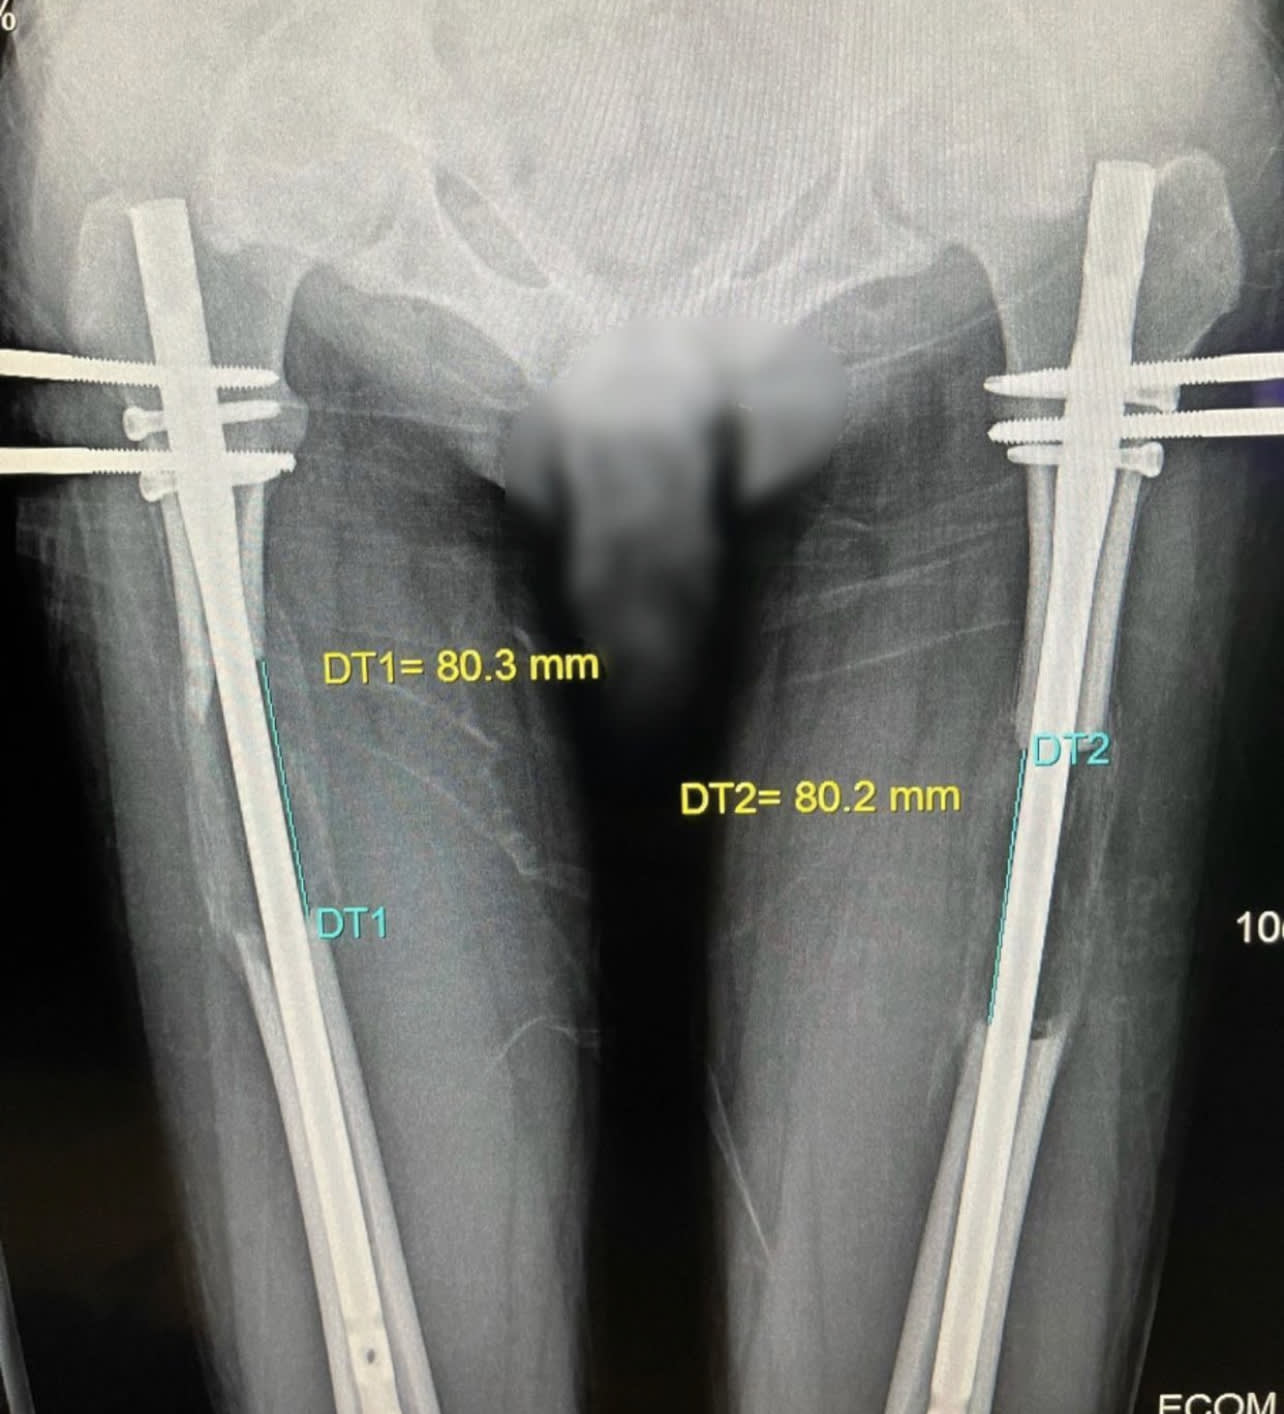

股骨肢体延长手术动画